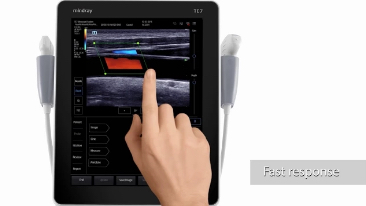

Esforzarse por una mejor atenciĂłn al paciente y buscar la mejor soluciĂłn para una decisiĂłn rĂĄpida es esencial para el personal clĂnico. Con herramientas inteligentes de gestiĂłn de fluidos, funciones para punciones seguras, una soluciĂłn completa de desinfecciĂłn e imĂĄgenes de calidad superior, el equipo Mindray TE7 ACE estĂĄ dise?ado para cubrir las aplicaciones de anestesia, cuidados crĂticos y emergencias. Listo para prestar atenciĂłn en cualquier momento, fĂĄcil de aprender y usar, ayuda a enfrentar con confianza todos los desafĂos de los servicios mĂ©dicos de alta calidad. Por primera vez, el TE7 ACE como ecĂłgrafo puede conectarse sin problemas a su red clĂnica con todos los demĂĄs equipos.